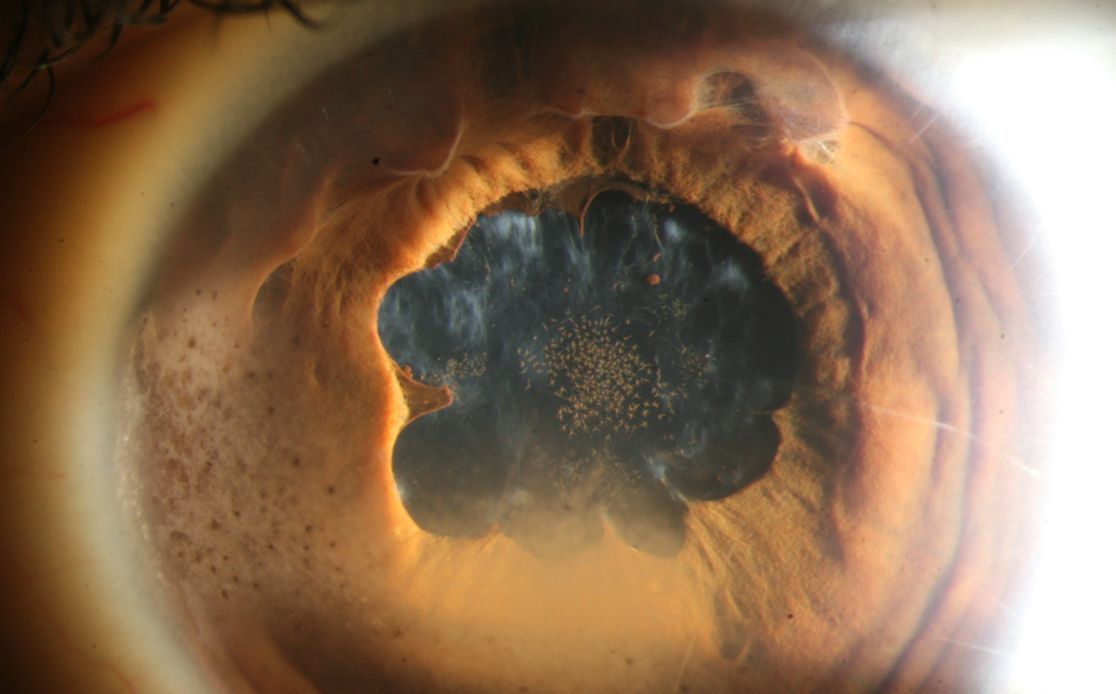

Netzhaut

Elektrophysiologiekurs

Der Kurs richtet sich an augenärztliches Fachpersonal, die ihr Wissen im Bereich der elektrophysiologischen Untersuchungsmethoden verbessern oder auffrischen möchten. In diesem Kontext wird auch das Thema der Erblichen Netzhautdegenerationen dargestellt.